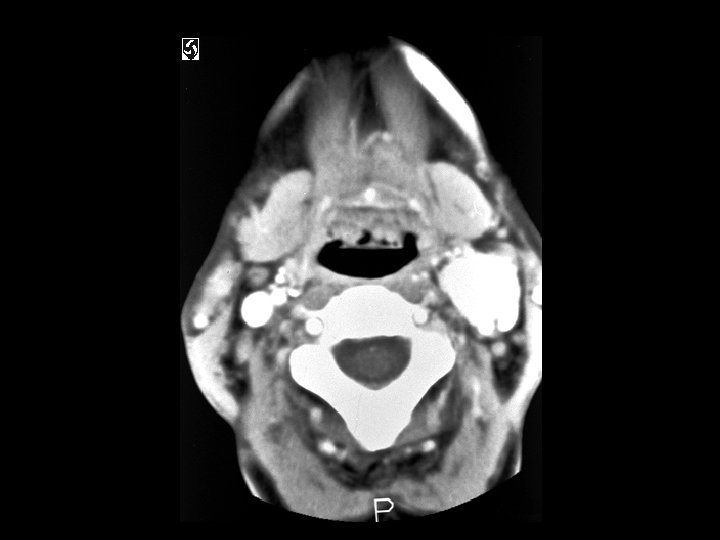

Carotid body paraganglioma • • Findings: – Intensely enhancing mass in the carotid sheath that splays the internal and external carotid arteries ddx: – Glomus vagali – Carotid aneurysm